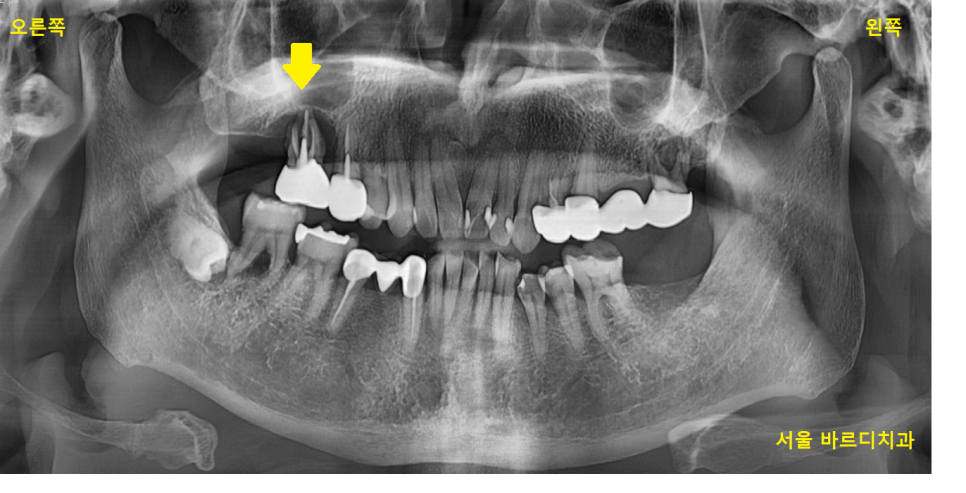

명일역 근처 치과 환자분이 처음 내원하셨을 때 사진입니다.

오른쪽으로 식사를 거의 못한다고 하셨습니다.

23.10.05

오른쪽 위아래 어금니 모두 문제가 있었습니다.

23.10.24

명일역 근처 치과에서 CT를 찍어보았을 때

하얀것이 뼈인데

치아 뿌리 부분으로 까만 것이 보이시죠?

주변 뼈가 다 녹을 정도로

고생하시다 오셨더라고요.